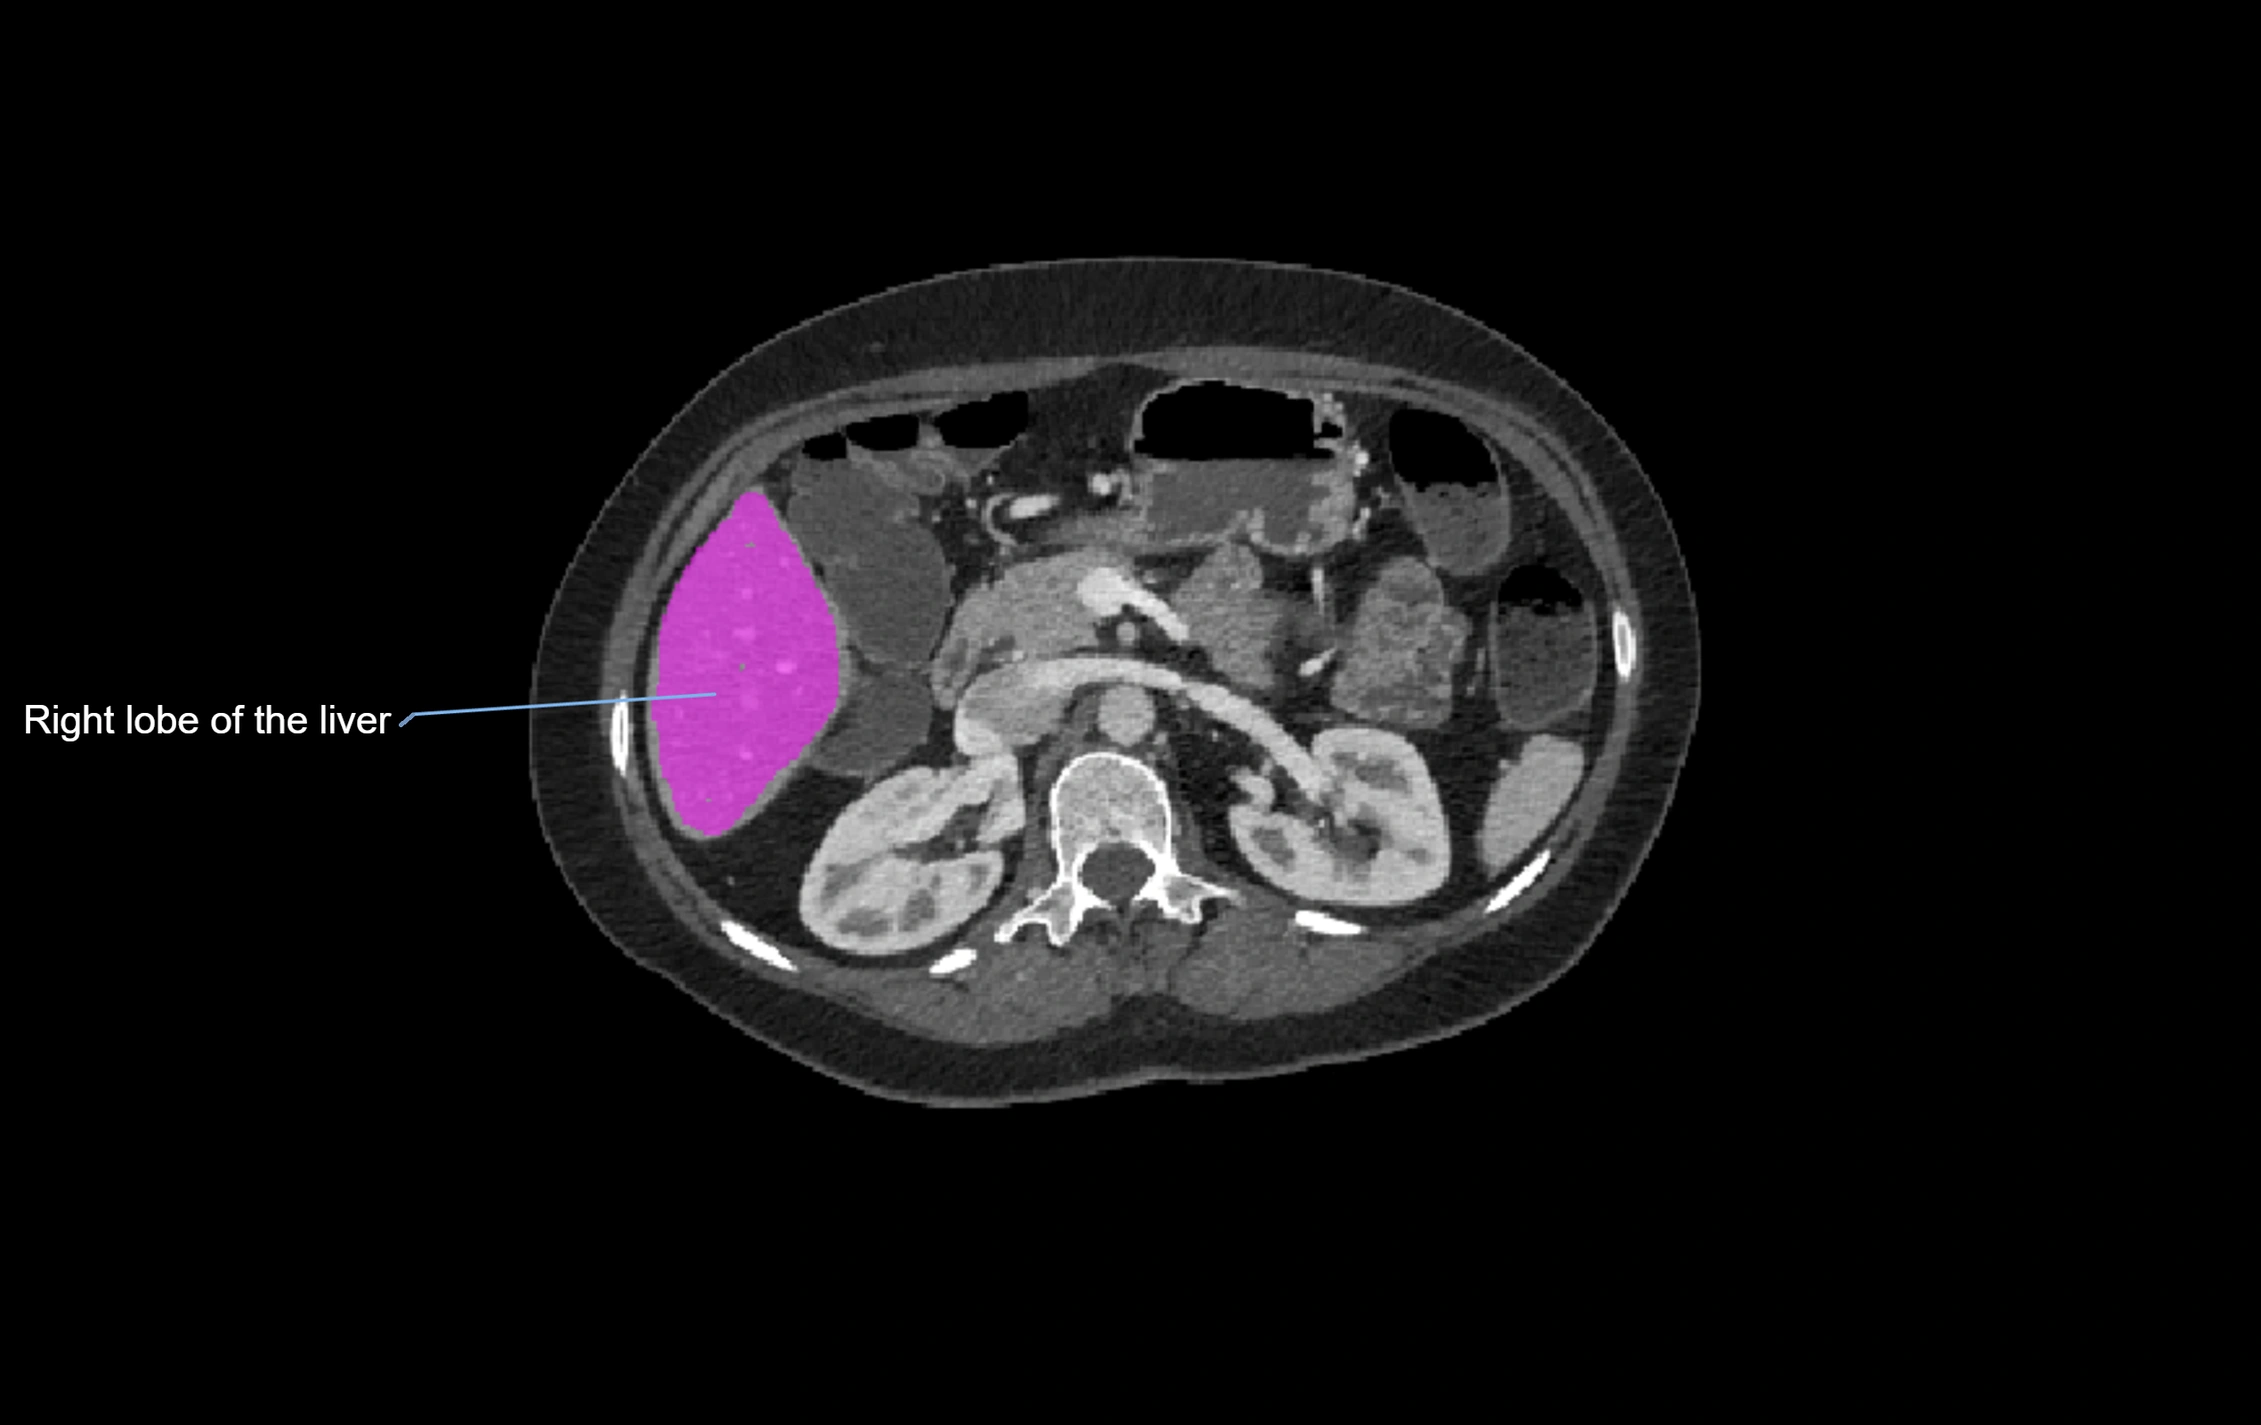

CT Appearance

CT Pre-Contrast:

• Caudate lobe appears as a soft-tissue density, isodense to the rest of the liver

• Enlargement may be appreciated in cirrhosis or Budd–Chiari syndrome

CT Post-Contrast:

• Homogeneous enhancement in the portal venous phase, similar to rest of liver

• Independent venous drainage into the IVC may be visualized

• Lesions follow characteristic CT enhancement patterns (HCC: arterial hyperenhancement with washout; hemangiomas: peripheral nodular enhancement with centripetal fill-in)

CT Venous Phase (functional significance):

• Caudate lobe often enhances relatively more than other lobes in Budd–Chiari syndrome, due to preserved venous outflow